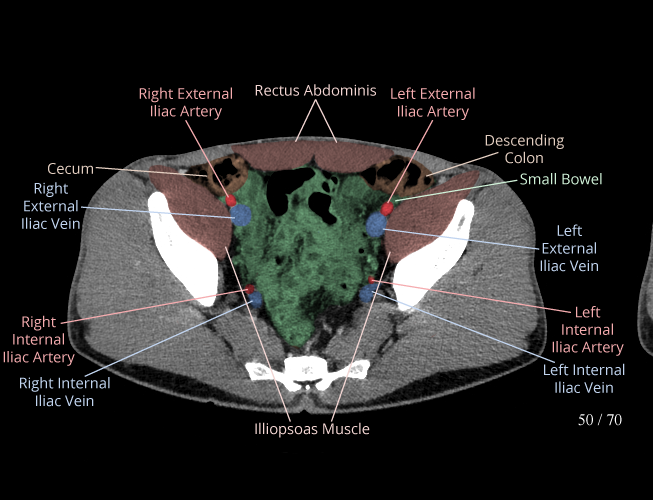

Body

Covers abdominal CT anatomy.